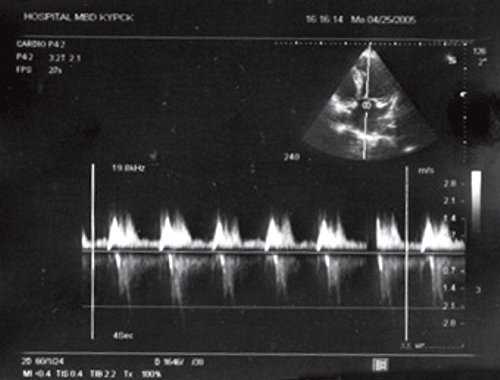

![Транстрикуспидальный поток у больного П (постоянноволновая допплерография)]()

Рис. 3. Транстрикуспидальный поток у больного П. (постоянноволновая допплерография).

При проведении эхокардиографии в месте обычного расположения левого желудочка лоцировался анатомически правый желудочек, который верифицировался по наличию модераторного пучка. Анатомически правый желудочек соединялся с левым предсердием через трикуспидальный клапан, который лоцировался ближе к верхушке сердца по сравнению с митральным клапаном. Последний соединял морфологически левый желудочек с правым предсердием, в который впадала нижняя полая вена (рис. 1). Определялся параллельный ход магистральных артерий, при этом аорта лоцировалась слева и спереди от легочной артерии. Таким образом, имело место предсердно-желудочковое и желудочково-артериальное несоответствие. У пациента выявлялась также недостаточность митрального и трикуспидального клапанов. На последнем клапане отмечалось увеличение градиента давления (рис. 2, 3).